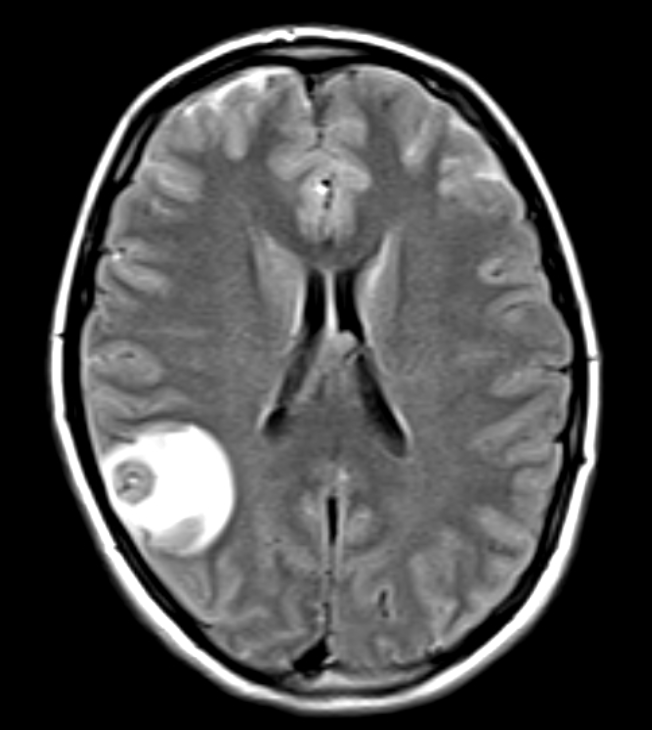

What are the imaging findings:

Scolex: part of tanea solium worm that attaches with 4 suckers along with an engancing lesion with vasogenic edema (consistent with degenerating cyst).